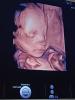

Я ходила на 25-26 недель